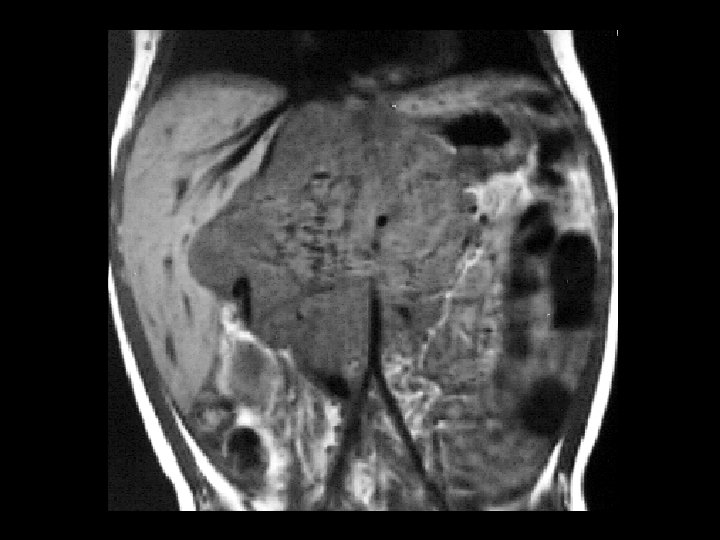

Neuroblastoma • Findings: – Bone scan shows increased uptake in the mid abdomen of a child – MR scan shows a corresponding soft tissue mass with scattered T 1 low sign foci = Ca 2+ • ddx: – NONE! – This is an Aunt Minnie!